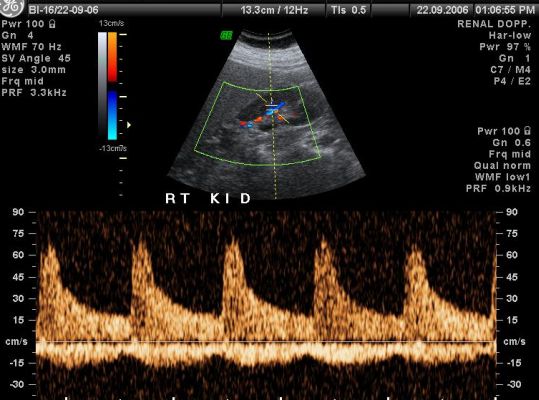

- RENAL ARTERY

In color Doppler the blood circulation is assessed. It is more often done in diabetic patients, in chronic smokers who are more prone to develop blockage in their arteries, in patients who suffer from varicose vein problem.

It is non invasive test which tells you about blood circulation to any particular part of the body like upper limb, lower limb, blood supply to any tumor or swelling involving the body.

Peripheral and carotid color Doppler does not need any special preparation, except for renal Doppler where patient has to be empty stomach for 4-6 hours.